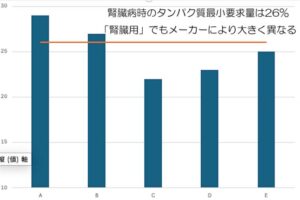

腎臓病食の選び方